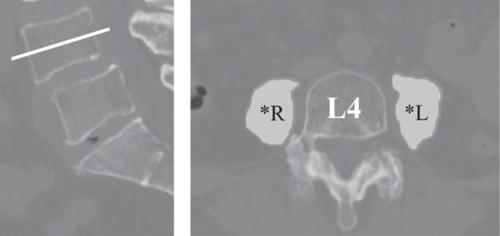

This retrospective study included 244 patients who underwent primary total hip arthroplasty with a minimum follow-up of 24 months. Spinopelvic mobility was assessed using changes in sacral slope during postural transitions, classified as stiff (<10°), normal (10°–30°), or hypermobility (≥30°). Osteosarcopenia was defined by psoas muscle area on computed tomography and lumbar bone mineral density. Outcomes were assessed using the EuroQol 5-Dimension and the Hip Disability and Osteoarthritis Outcome Score–Joint Replacement. Multivariate logistic regression analysis was performed to identify predictors of a patient-acceptable symptom state achievement on the EuroQol 5-Dimension. Propensity score matching yielded 35 patients with limited mobility and 70 controls.